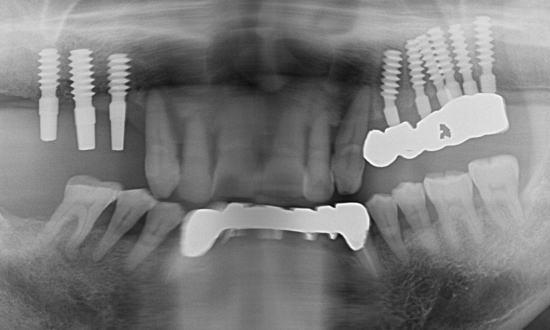

右上インプラント破折。このままインプラントを撤去すると、骨や歯肉の喪失が多くなるので、補綴物だけ外して、垂直+頬舌方向に骨造成を行う。

骨造成を行ってから、インプラントを撤去。骨幅が大きくなっているので、従来のインプラントより直径の太い物を植立して、破折防止。

破折したインプラントを除去すると、骨の喪失が大きくなるので、撤去する前に造骨してから撤去すると、その後には、従来のインプラントより直径の大きいインプラントが可能になります。